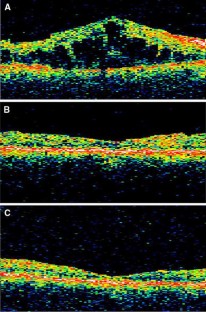

Figure 3